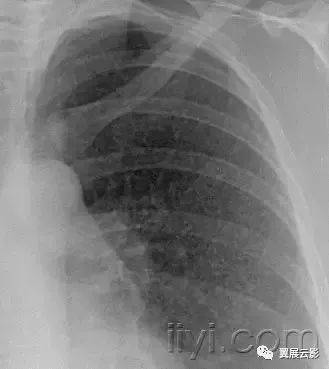

四十一、nodular pattern 粟粒样结节影

本名词尚未明确如何翻译好

平片和CT:粟粒样结节影表现为胸片上无数的小圆形结节,分布弥漫,指教解郁2~10mm内(图)。病变分布广泛但是不一定均匀,在CT上具有三种解剖分布模式:小叶中心性、沿淋巴管或者随机。